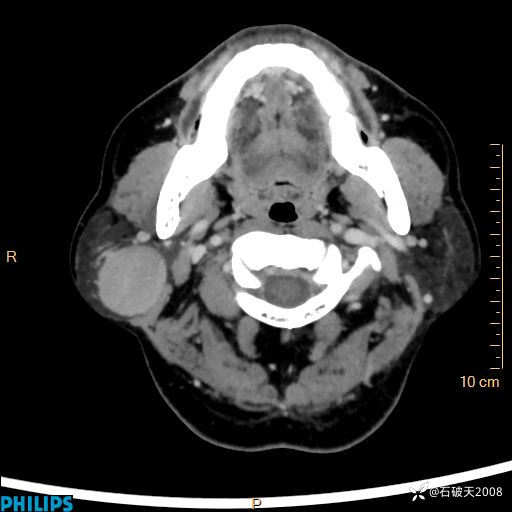

MIP